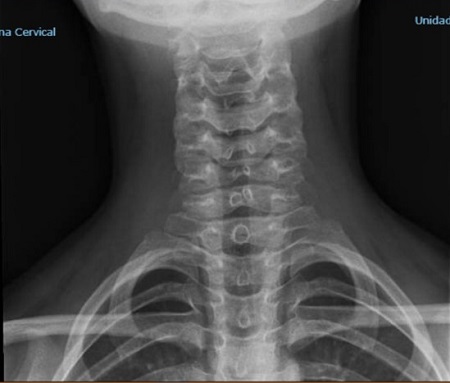

Paciente varón de 12 años de edad que acude por dolor cervical de varias semanas de evolución, que relaciona directamente con un viaje mochilero a Indonesia. El dolor no se irradia y no se acompaña de déficit sensitivo ni motor a ningún nivel. En la exploración se demuestra la presencia de contracturas musculares de ambos músculos trapecios, con movilidad del cuello conservada en todos sus planos. Tras una semana de medicación antiinflamatoria y medidas físicas, el dolor se mantiene, por lo que se solicita radiografía de columna cervical observándose apófisis espinosas de C3-C6 no fusionadas. Ante dicho hallazgo se realiza RMN de columna, donde no se objetiva defecto del cierre del arco posterior, por lo que es diagnosticado de espina bífida oculta cervical o defecto de fusión vertebral (Figura 1).

Espina bífida oculta cervical o defecto de fusión vertebral